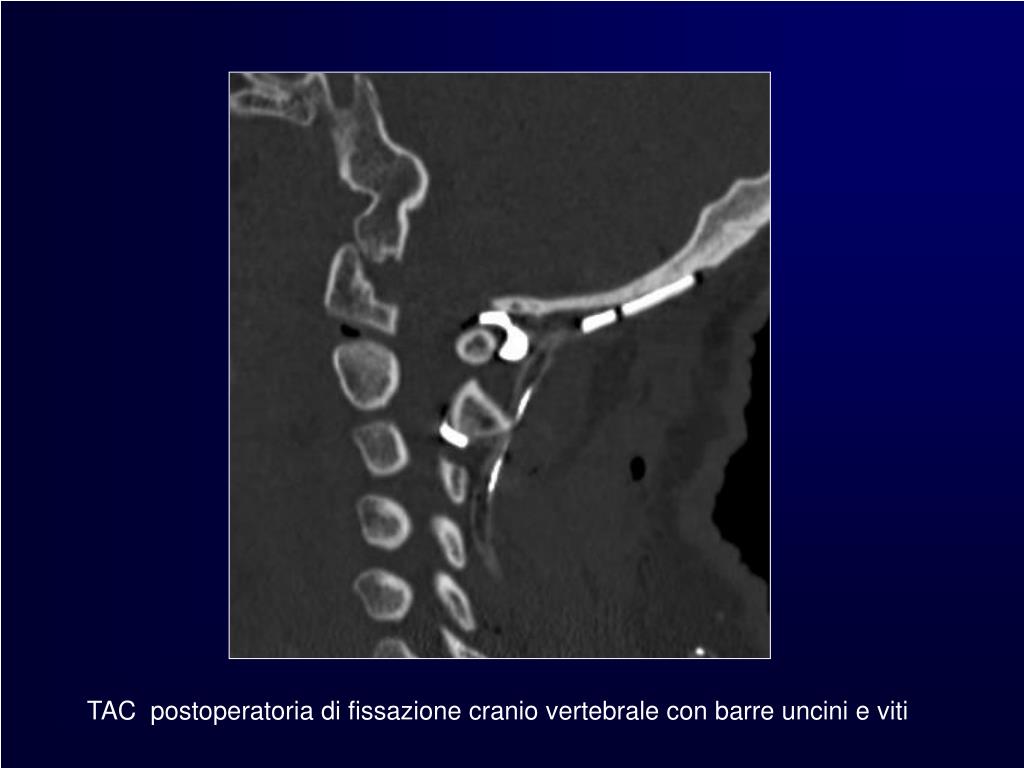

7. TAC postoperatoria di fissazione cranio vertebrale con barre uncini e viti